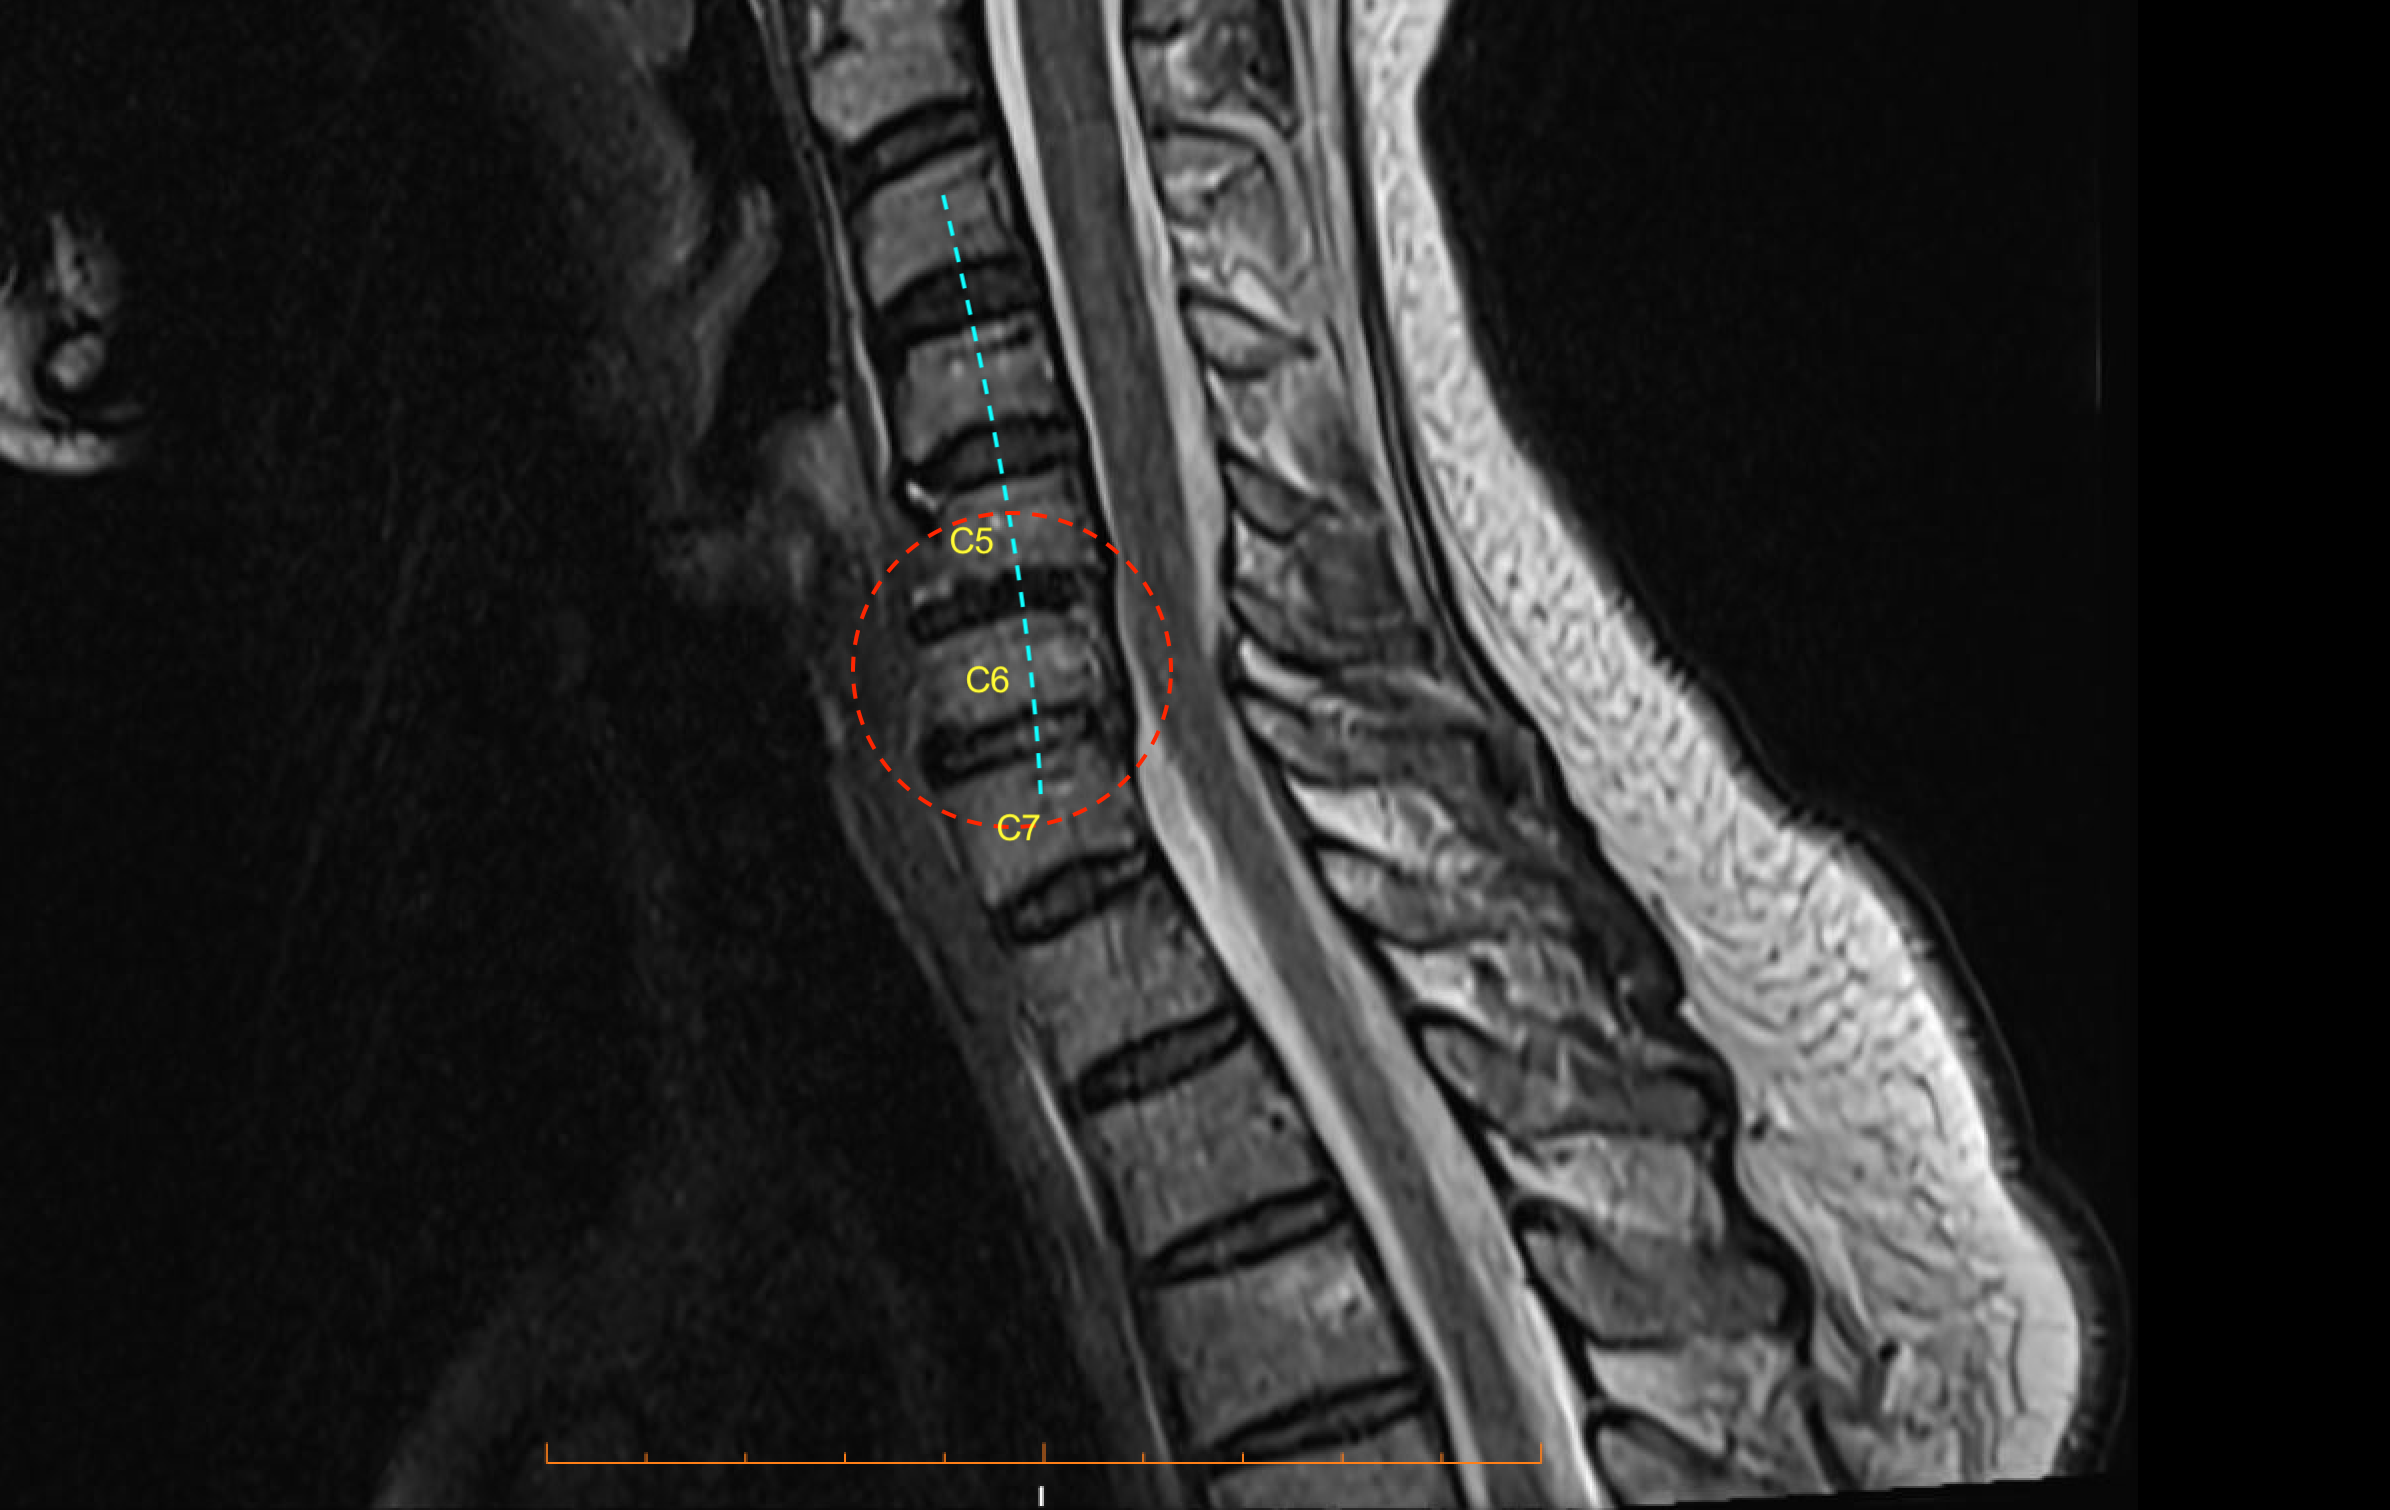

The pre-operative image (below) shows reversal of cervical spinal lordosis (blue dashed line) and loss of cervical disc heights at C5/6 and C6/7 in particular (red dashed oval). There is mild retrolisthesis at C5/6, with ‘shaggy’ endplate degeneration there.